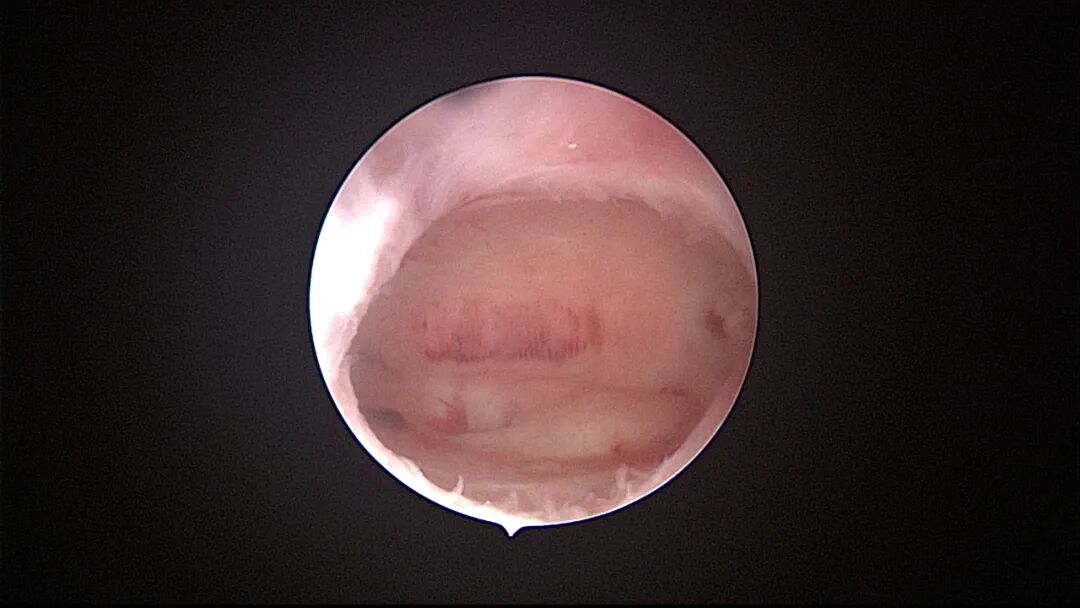

外院取环失败,子宫穿孔,盆腔积血

为了宫腔镜手术平稳顺利进行,宫腔镜术前准备及安全评估非常重要,尤其是充分的安全评估能有效减少并发症的发生。阴道情况:萎缩、纵膈、斜膈等可能导致扩阴器置入困难。肥胖病人、高个子病人阴道很深,宫颈可能难以暴露;宫颈情况:绝经后病人宫颈萎缩、狭窄、坚硬,加之穹隆展平,宫颈难以夹持、难以扩张;宫颈管弯曲、宫颈肌瘤、巨大息肉、粘膜皱襞隐窝、巨大纳囊等,可能阻挡宫腔镜进入宫腔;子宫情况:子宫萎缩,宫腔狭小,子宫极度前屈、后屈、侧屈等极端位置常常导致宫腔镜置入困难;既往盆腔手术史:子宫与盆腔器官粘连可能导致子宫极端位置,或者宫深超出预期。近期手术情况:外院取环失败、人流不全、宫腔探查或试图分粘中途放弃等病人,子宫可能存在假道、穿孔或盆腔积血等损伤。这类病人评估重点:前次手术医院级别、既往分娩情况、安环多少年、月经情况、闭经或绝经时间、手术日期、手术时间长短、是否麻醉、术后有无腹痛、有无阴道出血、B超情况、腹部平片、血糖血压等。宫腔镜术前需再次复查B超,手术医生到B超室了解子宫位置、大小、有无损伤、节育环种类及位置、是否嵌顿、盆腔有无积液等细节。

宫腔操作假道发生率较高,穿孔发生率较低,假道和穿孔原因一致,力度大了就穿孔了。假道或穿孔大多发生在门诊取环、人流、清宫等病例,尤其是绝经后取环占比最多。子宫位置特殊、宫颈管狭窄,探针探查、扩宫或取环钩操作时形成假道或穿孔,立即停止操作,经评估后做宫腔镜处理。宫腔操作动作要轻柔,注意子宫收缩节律,不要在子宫收缩时突然进入宫腔。穿孔可能损伤宫底或宫腔前后壁血管,缓慢持续出血导致盆腔积血。穿孔后是否探查盆腔、修补子宫需详细评估病情:血常规、B超、腹部刺激症状、失血体征、后穹隆穿刺等,大多数穿孔不需要手术探查。宫腔镜术中出现难以控制的出血大多发生于靠近子宫动静脉的粘膜下肌瘤、侧壁宫腔粘连、胚物残留合并动静脉瘘及子宫纵膈手术等,直视下电凝止血是最佳办法,球囊压迫止血影响因素太多,包括出血部位、动静脉区别、血管大小、子宫收缩情况、球囊大小、牵拉球囊力度等,效果一言难尽,尽量不采用。腹腔镜下缝合子宫壁、经阴道宫颈侧壁缝合(都不一定能缝到出血血管)、艾丽斯钳钳夹宫颈等方法可压迫止血或明显减少出血。手术越熟练、缩短手术时间、快速完成手术,手术越安全,避免严重水中毒发生。甘露醇或5%葡萄糖膨宫,手术每隔20~30分钟,建议速尿(半衰期为30~60分钟)半支静推;生理盐水膨宫,手术时间持续30~45分钟,速尿半支静推,总时间最好控制在60分钟以内,不要超过90分钟,必要时分次手术。速尿具体使用量及间隔时间根据膨宫介质、膨宫压力、手术难易及时间长短、创面及血管暴露情况、病人生命体征、麻醉情况等决定。